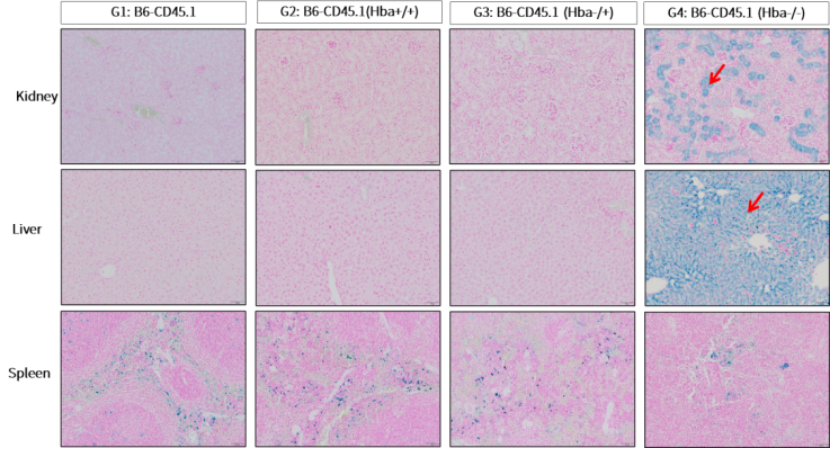

重度表型(Hb Bart’s胎儿水肿综合征模型):完全的α珠蛋白双基因敲除(即纯合敲除,小鼠体内无任何α链)在胚胎期具有致死性,相当于人类的Hb Bart’s胎儿水肿综合征。集萃药康采用胎肝细胞重建模型,将来源于胚胎第13.5天的肝脏造血干细胞移植到经放射线清髓的受体小鼠体内,以在成年小鼠中重建纯合敲除胚胎的造血系统。移植纯合敲除(Hba-/-)胎肝细胞的小鼠(G4组)在移植后第9周,小鼠存活率仅40%(图3a),其肝、脾、肾相对重量均显著高于对照组,提示明显的肝脾肾肿大和可能的髓外造血现象(图3b)。

血液学检查显示G4组外周血重度贫血,RBC (Red Blood Cell Count, 红细胞计数)略有升高,HGB先下降后上升,MCV升高,HCT (Hematocrit, 红细胞压积)升高,MCH先下降后上升,RETIC升高(图4)。这些变化与文献报道的人类重度α-地贫的血液学特征一致。脏器病理方面,G4组小鼠的肝和肾脏也出现显著铁沉积(普鲁士蓝染色阳性信号显著增强),进一步证明了重度无效造血导致的铁过载(图5)。因此该胎肝移植模型在成年小鼠中再现了人类Hb Bart’s水肿胎的血液学和病理特征,可用于评估基因治疗等在体干预对重型α-地贫的疗效。

图5 胎肝细胞重建小鼠普鲁士蓝染色分析